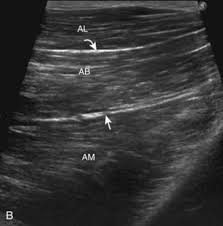

Written by keith bridwell, md; Anatomy of the whole body (neck, thorax, abdomen and pelvis) on a positron emission tomography with 250 anatomical structures of the neck and trunk were labeled using only the visible structures the veins include the upper and lower vena cava system as well as the portal system. The chewing muscles enable you to chew your food by moving the upper and lower teeth against one another. Anatomynote.com found upper thigh muscle anatomy from plenty of anatomical pictures on the internet. Muscles that move the shoulder and arm include the trapezius and serratus anterior. Upper thigh muscles ct anatomy : Anatomy of the muscular system. This view here just shows the medial compartment muscles of the thigh.

Upper thigh muscles ct anatomy : Want to learn more about it? Upper body muscle anatomy conclusions. Nine muscles cross the shoulder joint to move the upper arm. Dummies helps everyone be more knowledgeable and confident in applying what they know. Muscles of the posterior cervical and upper thoracic spine 1. Muscles adapted for loaded versus unloaded actions. The upper limb muscles fall into three groups. A complete list of muscular system quizzes; 2, vastus medialis & intermedius muscles. I'll be flicking between the two models. Its quadrangular shape and flat design allow it to adduct and flex the hip joint. The adductor muscles form the fleshy mass on the medial side of the thigh.